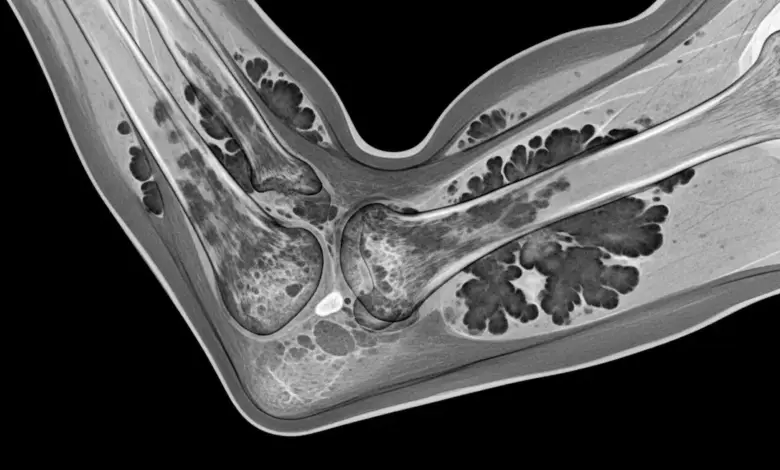

- Ressonância magnética: método de escolha para mapear o acometimento sinovial; costuma exibir áreas com depósito de pigmento e realce após contraste.